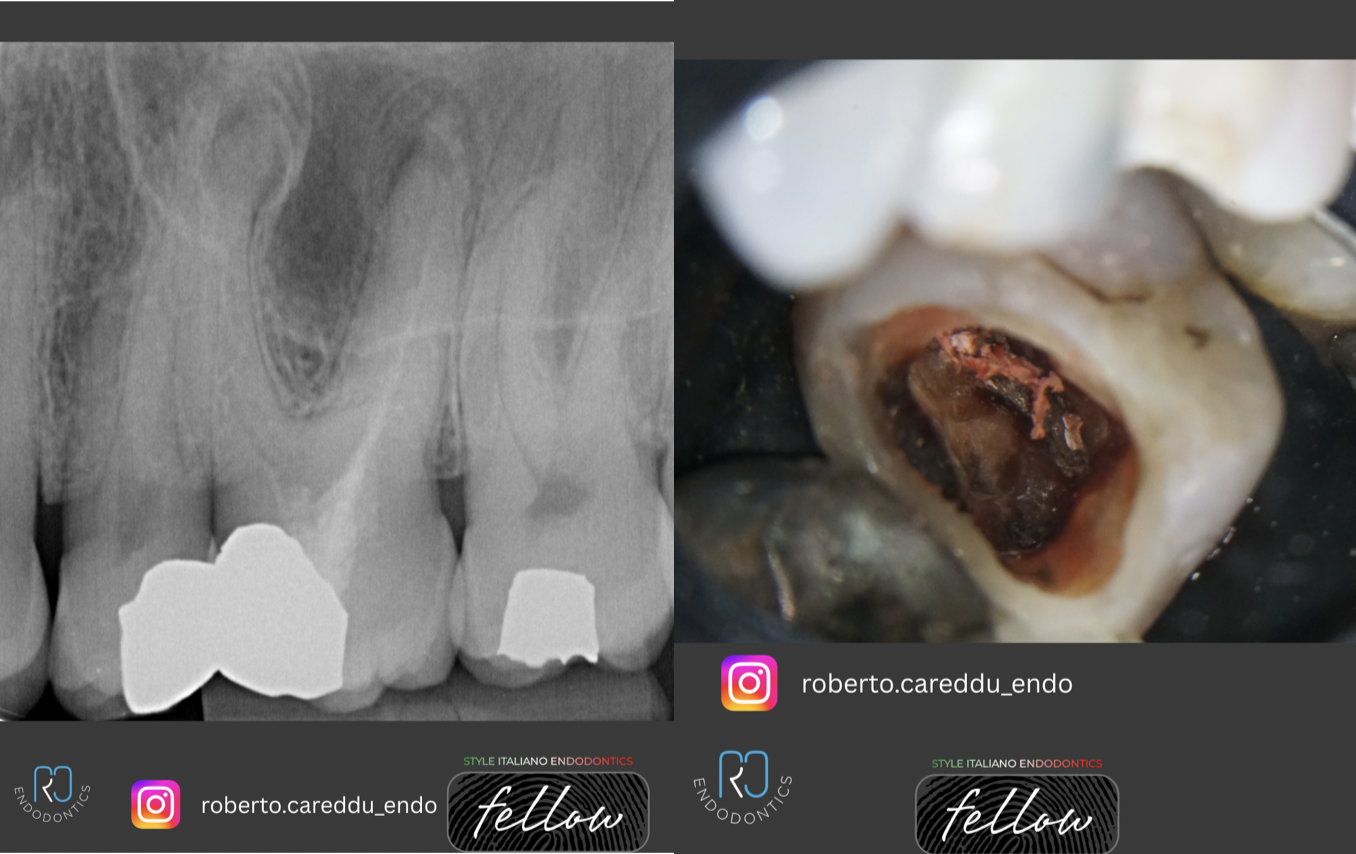

Fig. 1

The patient was referred for retreatment of symptomatic tooth 26, which presented with a periapical radiolucency (PARL). The tooth exhibited the characteristic reddish discoloration associated with the use of “Russian Red” material. The treatment had been carried out in the 90s in a Easter European Country

Fig. 2

The existing amalgam restoration was removed, and access to the pulp chamber was established. The material was then carefully removed using ultrasonic tips and austenitic rotary files. The canal system was shaped and irrigated with sodium hypochlorite (NaOCl) and EDTA, with sonic activation to enhance effectiveness. The canals were subsequently obturated using a hydraulic cement in combination with gutta-percha.